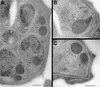

The members of the phylum Apicomplexa parasitize a wide range of eukaryotic host cells. Plasmodium falciparum, responsible for the most virulent form of malaria, invades human erythrocytes using several specific and high affinity ligand-receptor interactions that define invasion pathways. We find that members of the P. falciparum reticulocyte-binding homolog protein family, PfRh2a and PfRh2b, are expressed variantly in different lines. Targeted gene disruption shows that PfRh2b mediates a novel invasion pathway and that it functions independently of other related proteins. Phenotypic variation of the PfRh protein family allows P. falciparum to exploit different patterns of receptors on the erythrocyte surface and thereby respond to polymorphisms in erythrocyte receptors and to evade the host immune system.